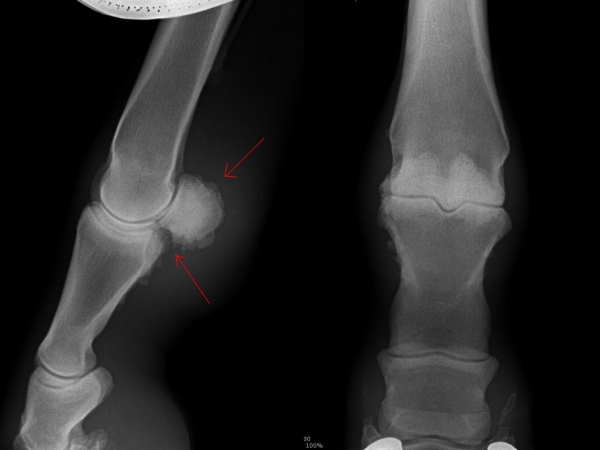

Fragment na spěnkové kosti

Čip ve spěnkovém kloubu na pánevní končetině

Ankylóza spěnkovýho kloubu

rentgenologické vyšetření

ohebové zkoušky